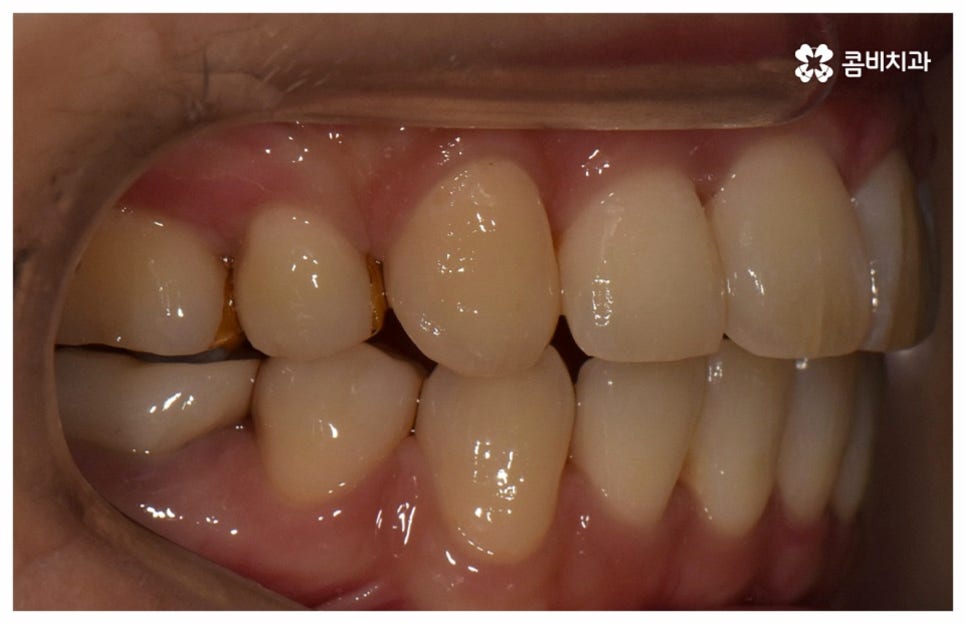

위 사진은 환자분의 동의를 받아 이해를 돕기 위한

사진이며, 실제 치료 결과는 다를 수 있습니다.